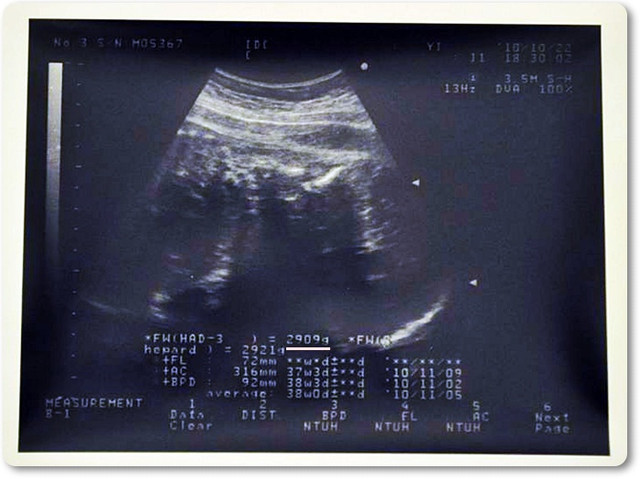

好...這禮拜的產檢

目前是37W又6D

醫師一樣是跟我們說

隨時可以準備生了![]()

麻麻最近就是要多走路,看能不能讓胎位早點下來

目前已有下來一點點囉![]()

咩羊的體重...

一個禮拜的時間...就大了300g內

目前已是2900g囉![]()

我們家麻麻覺得這樣的體重已經夠了,醫師也是這麼認為...

目標: 3000g-3200g就好![]()

不然太大隻,我們家麻麻要生的時候會比較辛苦內

2010.10.22 咩羊 37W6D